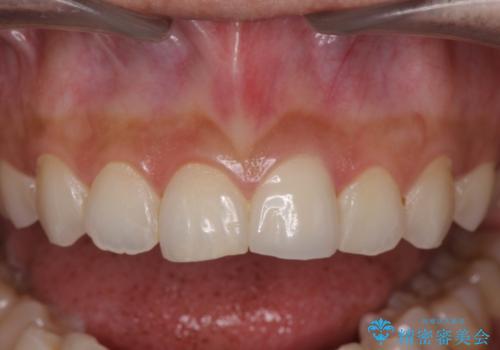

すり減った前歯の形態回復

- 13.2万円(ジルコニアクラウン・仮歯)費用は治療当時の料金となります

自然な色調のセラミッククラウンで審美性を回復することができ、大変満足いただけました。